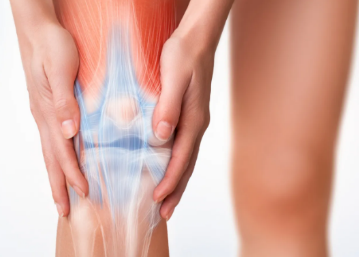

Gender Differences Mean More Knee Injuries for Women

Though men and women are equal, they're not the same—and that includes their knees. Those differences contribute to women athletes being more than twice as likely to tear their anterior cruciate ligament (ACL) as men, a figure that varies by sport. Female basketball players have a 3.5 times greater incidence of ACL tears...

How to Keep Your Knees Strong and Healthy

Despite being the largest joint in the human body, the knee can be underappreciated when it comes to daily exercise. After all, if you ask most folks what their workout routines consist of, they will probably tell you they do squats and lunges for glute and quad toning, planks and crunches for abdominal muscle...

Why are Women More Prone to Knee Injuries?

Anatomical and hormonal differences may be to blame, but there are ways to help reduce the risk. More recent research has indicated what we orthopedic surgeons have often seen in our practice: women are 2 to 9 times more likely than men to have certain kinds of knee problems. Generally, knee injuries are very...

ACL Tears in Girls and Women Athletes

Medical experts are still learning why certain groups are more prone to sports injuries than others. Women and girls—especially those who play soccer, basketball or softball—are more likely than boys and men to tear the anterior cruciate ligament (ACL), knee tissue that connects the thighbone to the shin and requires...